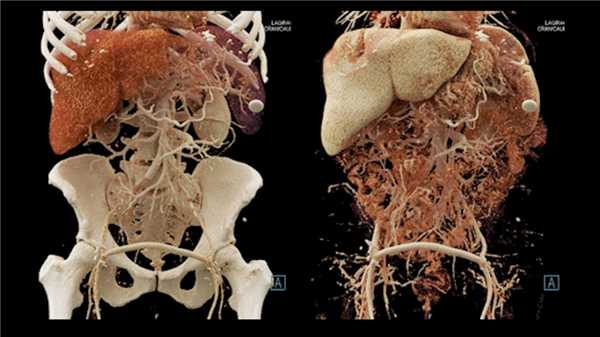

Другой метод — 3D-рендеринг, позволяющий восстановить из исходных данных, подходящих по определенный критерий (чаще всего это также структуры наивысшей плотности — кости и кровь, содержащая контрастное вещество) трехмерную модель. Работая на станции, радиолог может рассматривать модель со всех сторон и «отрезать» лишние фрагменты изображений. Одним из видов 3D рендеринга является виртуальная эндоскопия — технология, позволяющая вывести в трехмерном изображении полый орган (чаще всего проводят виртуальные колоноскопию и бронхоскопию). Это исследование не заменяет реальной скопической процедуры, но может предоставить дополнительные данные или помочь в планировании реальной процедуры.